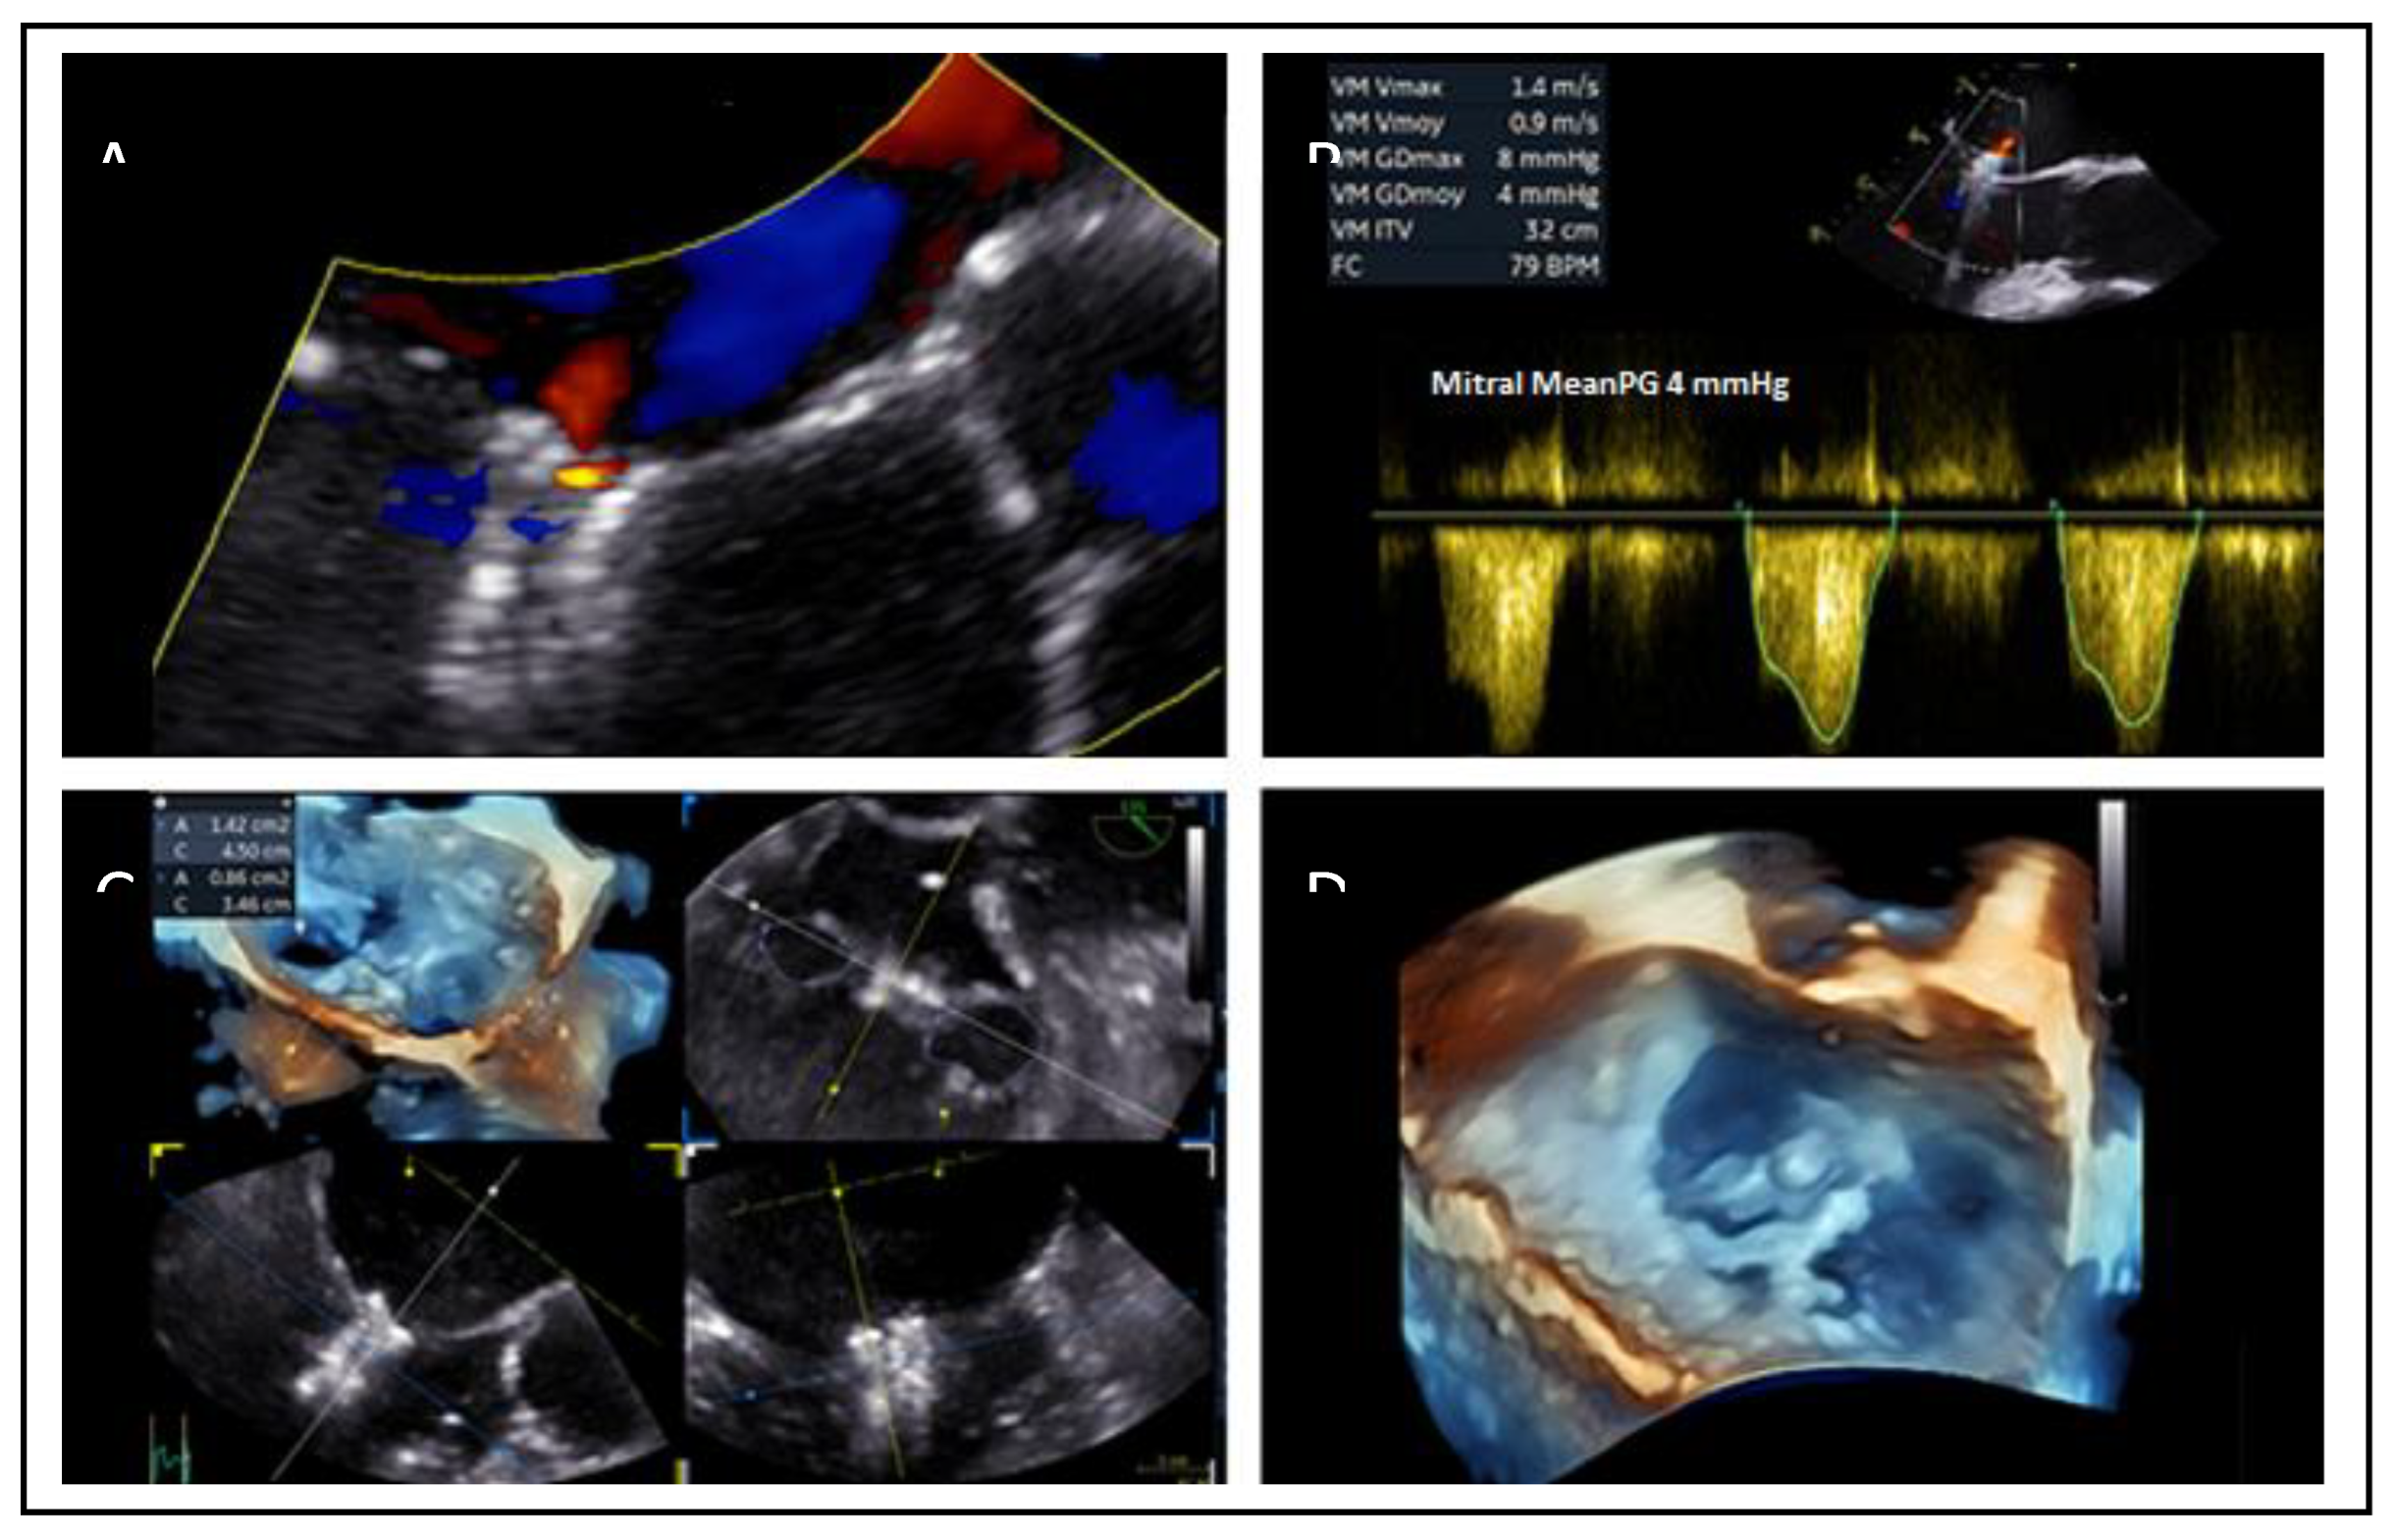

- Mitral valve area (MVA) and pressure gradient (PG): MVA <4.0 cm² may raise concern for post-procedural mitral stenosis, especially in patients requiring multiple devices. Cut-off values of 3.0cm2 for MVA and 4mmHg for mean PG are used to consider a patient ineligible for this method.

7.3. Mitral Valve Area and Gradient